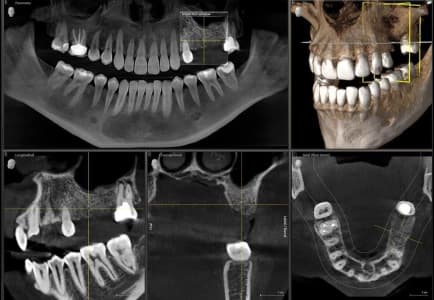

CBCT is a specialized type of X-ray technology that generates 3D images of your teeth, jaws, and facial structures with remarkable clarity.

See intricate anatomical structures, bone density, and pathology with unparalleled clarity.

Supports accurate implant placement, impacted tooth removal, and complex endodontic procedures.